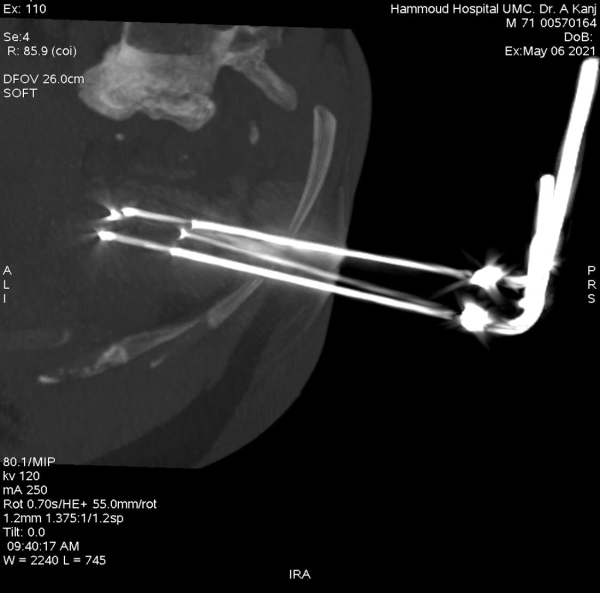

إنجاز طبي جديد في مستشفى حمود الجامعي لأول مرة في الجنوب، عبارة عن علاج ورم ضخم في الكلية مكون من كتلة سرطانية تتخطى ال٦ سنتم بالتقنية الحديثة Cryoablation Of Tumor Under CT

وهي تقنية تجميد وقتل الأورام السرطانية الخبيثة دون إجراء عملية جراحية ودون آلام.

قام بإجراء العملية الدكتورعلي كنج، رئيس قسم الأشعة في مستشفى حمود الجامعي، لمريض في العقد السادس من عمره من خلال تخدير موضعي حيث تمكن المريض من مغادرة المستشفى في اليوم الثاني. بعد نجاح العملية، أكد الدكتور كنج على أهمية هذه التقنية في علاج الأمراض السرطانية المختلفة كعلاج أساسي، أو كعلاج مساعد للعلاج الطبي وللتخلص من الآلام الناتجة من الأمراض السرطانية.